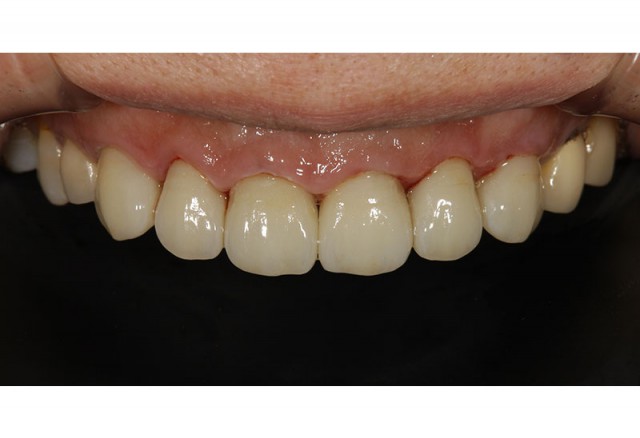

施術後

前歯6本を変更することで大変きれいな印象へと変わりました。オールセラミックは審美性に優れており、透明感やツヤがあり自然な色調で回復することができます。今回のような前歯には非常に相性が良い素材です。

また金属を使用しないので、金属アレルギーの方でも安心して使用いただけます。

オールセラミックは1本10万円からの施術となり今回は60万円での施術となりました。